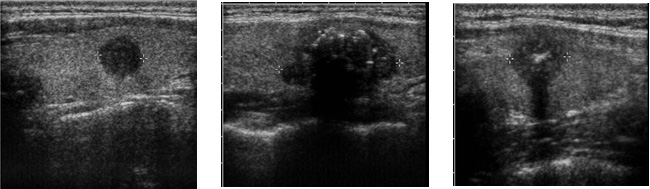

갑상선종양의 진단도가 가장 정확한 방법입니다. 갑상선 초음파 검사로 결절의 크기, 모양, 위치, 결절의 갯수 등을 알 수 있을 뿐 아니라 결절의 낭성 변화(혹 속에 피나 물이 고이는 경우)나 낭종(물혹)을 확인할 수 있습니다. 경계가 좋지 않은 결절, 내부에코가 불균등 한 경우 및 갑상선 밖으로 침범하는 모양을 보이는 멍울주위에 임파절이 커져있는 경우 갑상선 암을 의심할 수 있습니다.